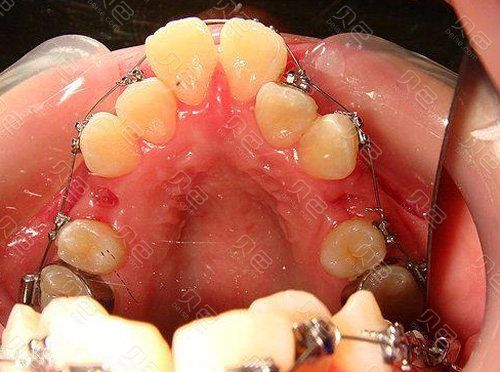

在拔牙正畸治疗中,T形曲(T-loop)的位置至关重要,因为它决定了施加在牙齿上的力量大小、方向和持续时间。没有绝对固定的位置,它需要根据具体的牙齿移动目标、拔牙模式、支抗需求和牙弓形态来精确设计。

最经典和常见位置:尖牙与第一前磨牙之间(第一前磨牙托槽远中)

- 垂直臂: 其近中端通常紧贴尖牙托槽的远中翼(或非常靠近尖牙托槽槽沟的远中边缘),这是施加力量点,直接作用于尖牙。

- 水平臂: 水平放置在第一前磨牙托槽的远中区域,水平臂本身不直接产生主要移动牙齿的力量,但它起到了重要的支抗作用,将垂直臂产生的力量传递给后牙支抗单位(磨牙),防止后牙前移过多,并为尖牙提供稳定的后移支抗。

- 常见位置: 尖牙与第一前磨牙之间(第一前磨牙托槽远中) 是远中移动尖牙时最经典、最常用的位置。